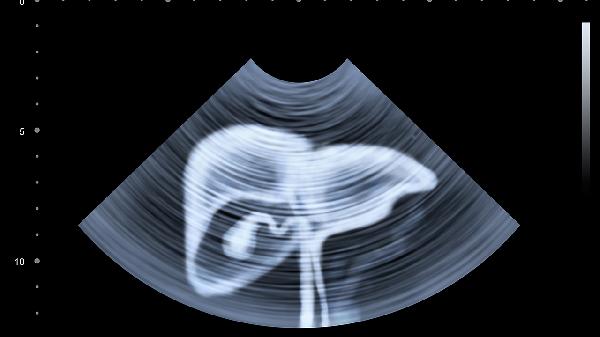

怎么样去除肝脏的毒素

去除肝脏毒素的关键在于改善生活方式、调整饮食结构以及必要时使用药物辅助。肝脏是人体的重要解毒器官,毒素积累可能由不良生活习惯、环境污染或疾病引起。通过合理饮食、适量运动、减少酒精摄入以及使用护肝药物,可以有效帮助肝脏排毒。